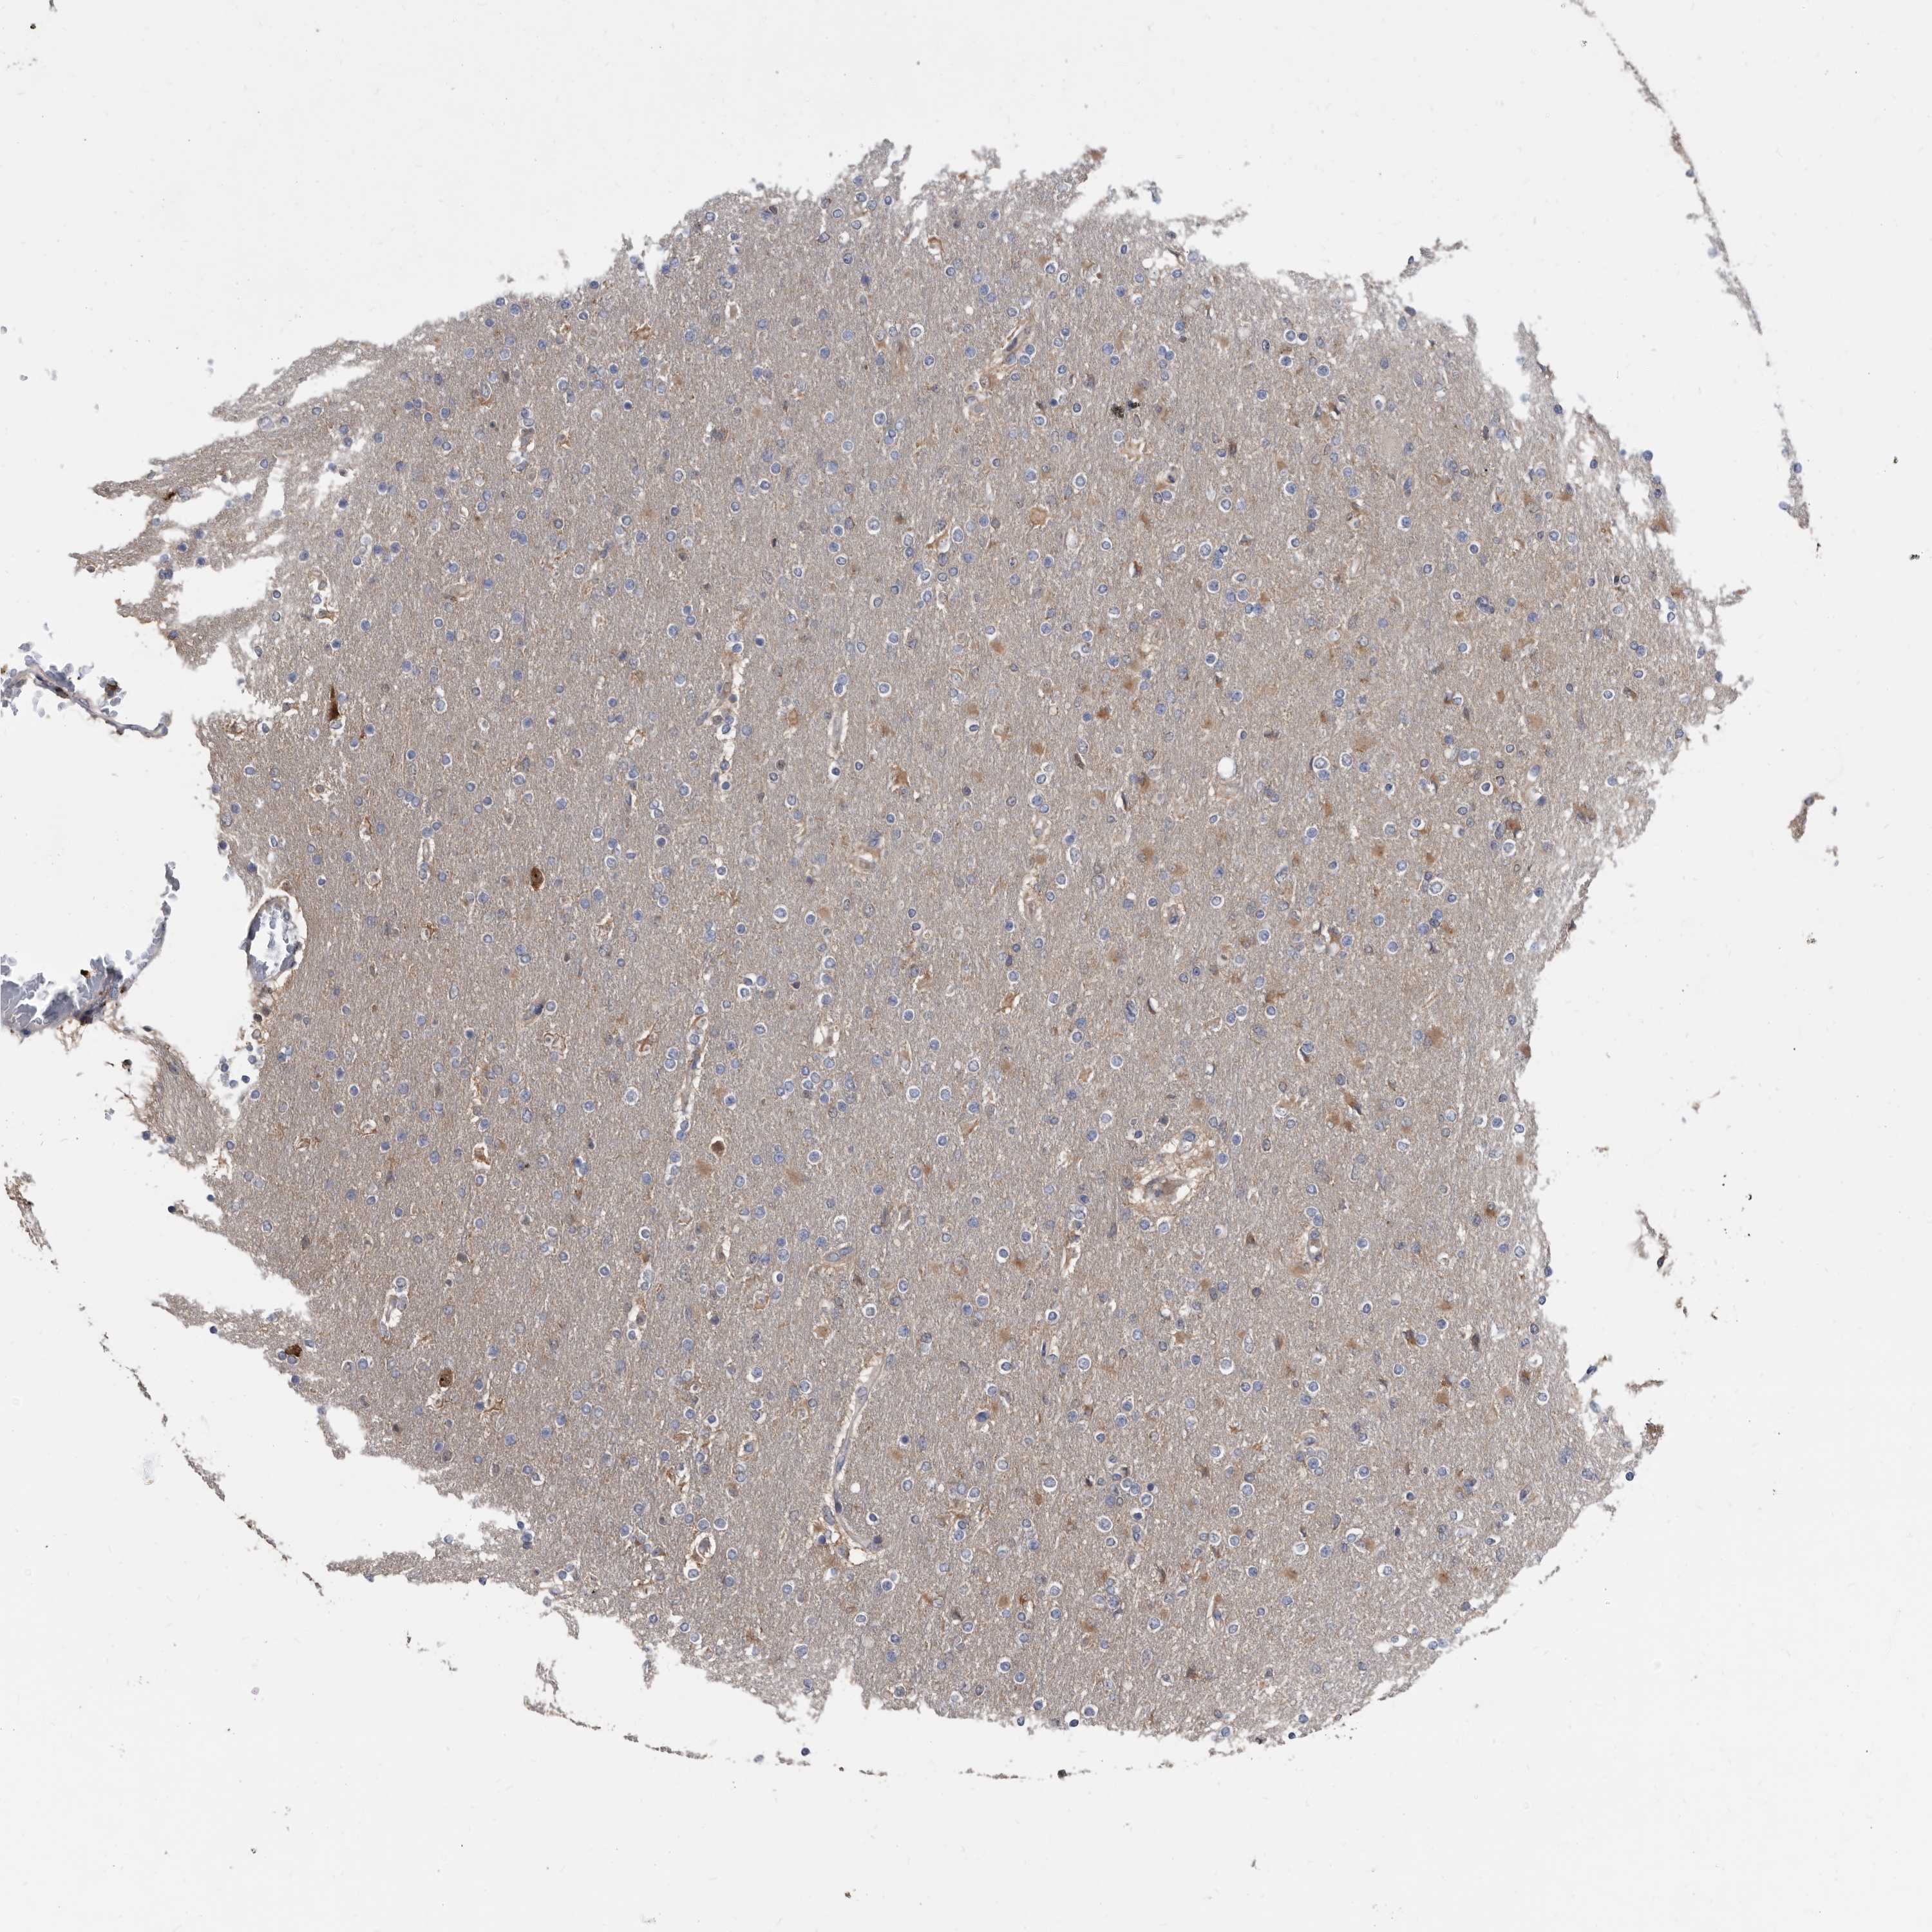

GLIOMA - Protein expressioni

A mouse-over function shows sample information and annotation data. Click on an image to view it in a full screen mode. Samples can be filtered based on level of antibody staining by selecting one or several of the following categories: high, medium, low and not detected. The assay and annotation is described here.

Note that samples used for immunohistochemistry by the Human Protein Atlas do not correspond to samples in the TCGA dataset.

Antibody stainingi

Antibody staining in the annotated cell types in the current human tissue is reported as not detected, low, medium, or high, based on conventional immunohistochemistry profiling in selected tissues. This score is based on the combination of the staining intensity and fraction of stained cells.

Each image is clickable and will lead to virtual microscopy that enables deeper exploration of all samples and also displays staining intensity scores, fraction scores and subcellular localization as well as patient and tissue information for each sample.

Antibody HPA029700

Antibody HPA029701

Antibody HPA029702

Antibody HPA029703

Staining

High

Medium

Low

Not detected

Intensity

Strong

Moderate

Weak

Negative

Quantity

>75%

75%-25%

<25%

None

Location

Nuclear

Cytoplasmic/membranous

Cytoplasmic/membranous,nuclear

Glioma, malignant, High grade

Glioma, malignant, Low grade

Glioblastoma, NOS